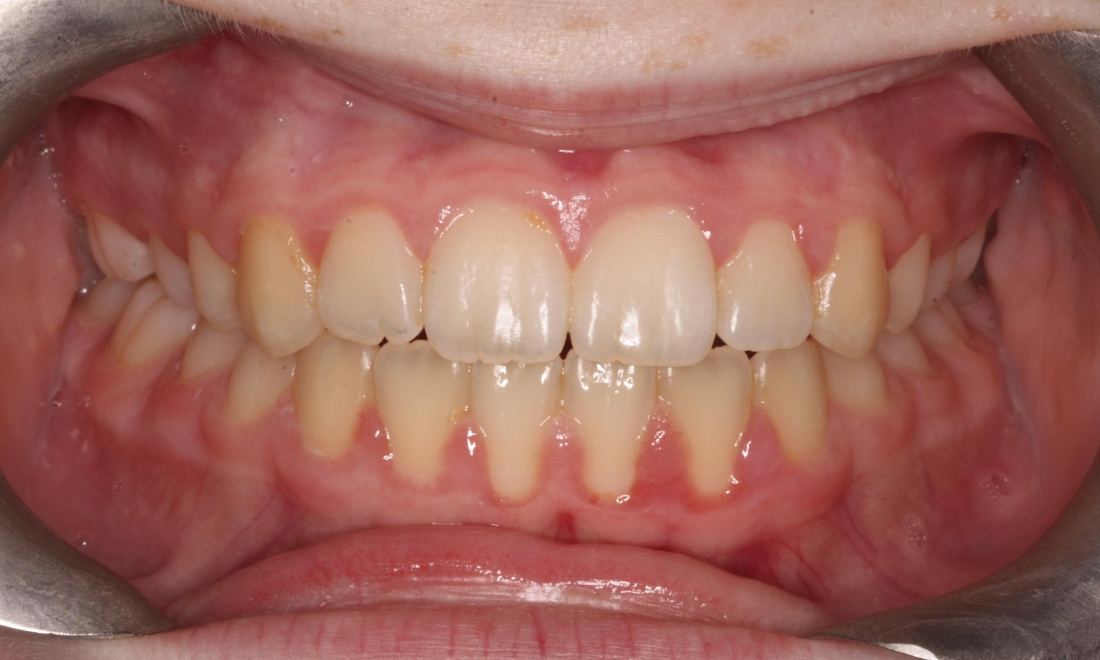

This patient had a narrow upper jaw which was expanded using an RME appliance and fixed appliances to align and level the arches. Total treatment time was 34 months